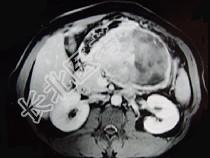

- 单项选择题男,36岁, 腹胀、消化不良、消瘦、中上腹痛,影像检查如下图, 最可能的诊断为 ( )

A、胃间质瘤并肝血管瘤

B、胃淋巴瘤伴原发性肝癌

C、胃间质瘤并原发性肝癌

D、内胚窦瘤肝转移

E、胃间质肉瘤并肝转移